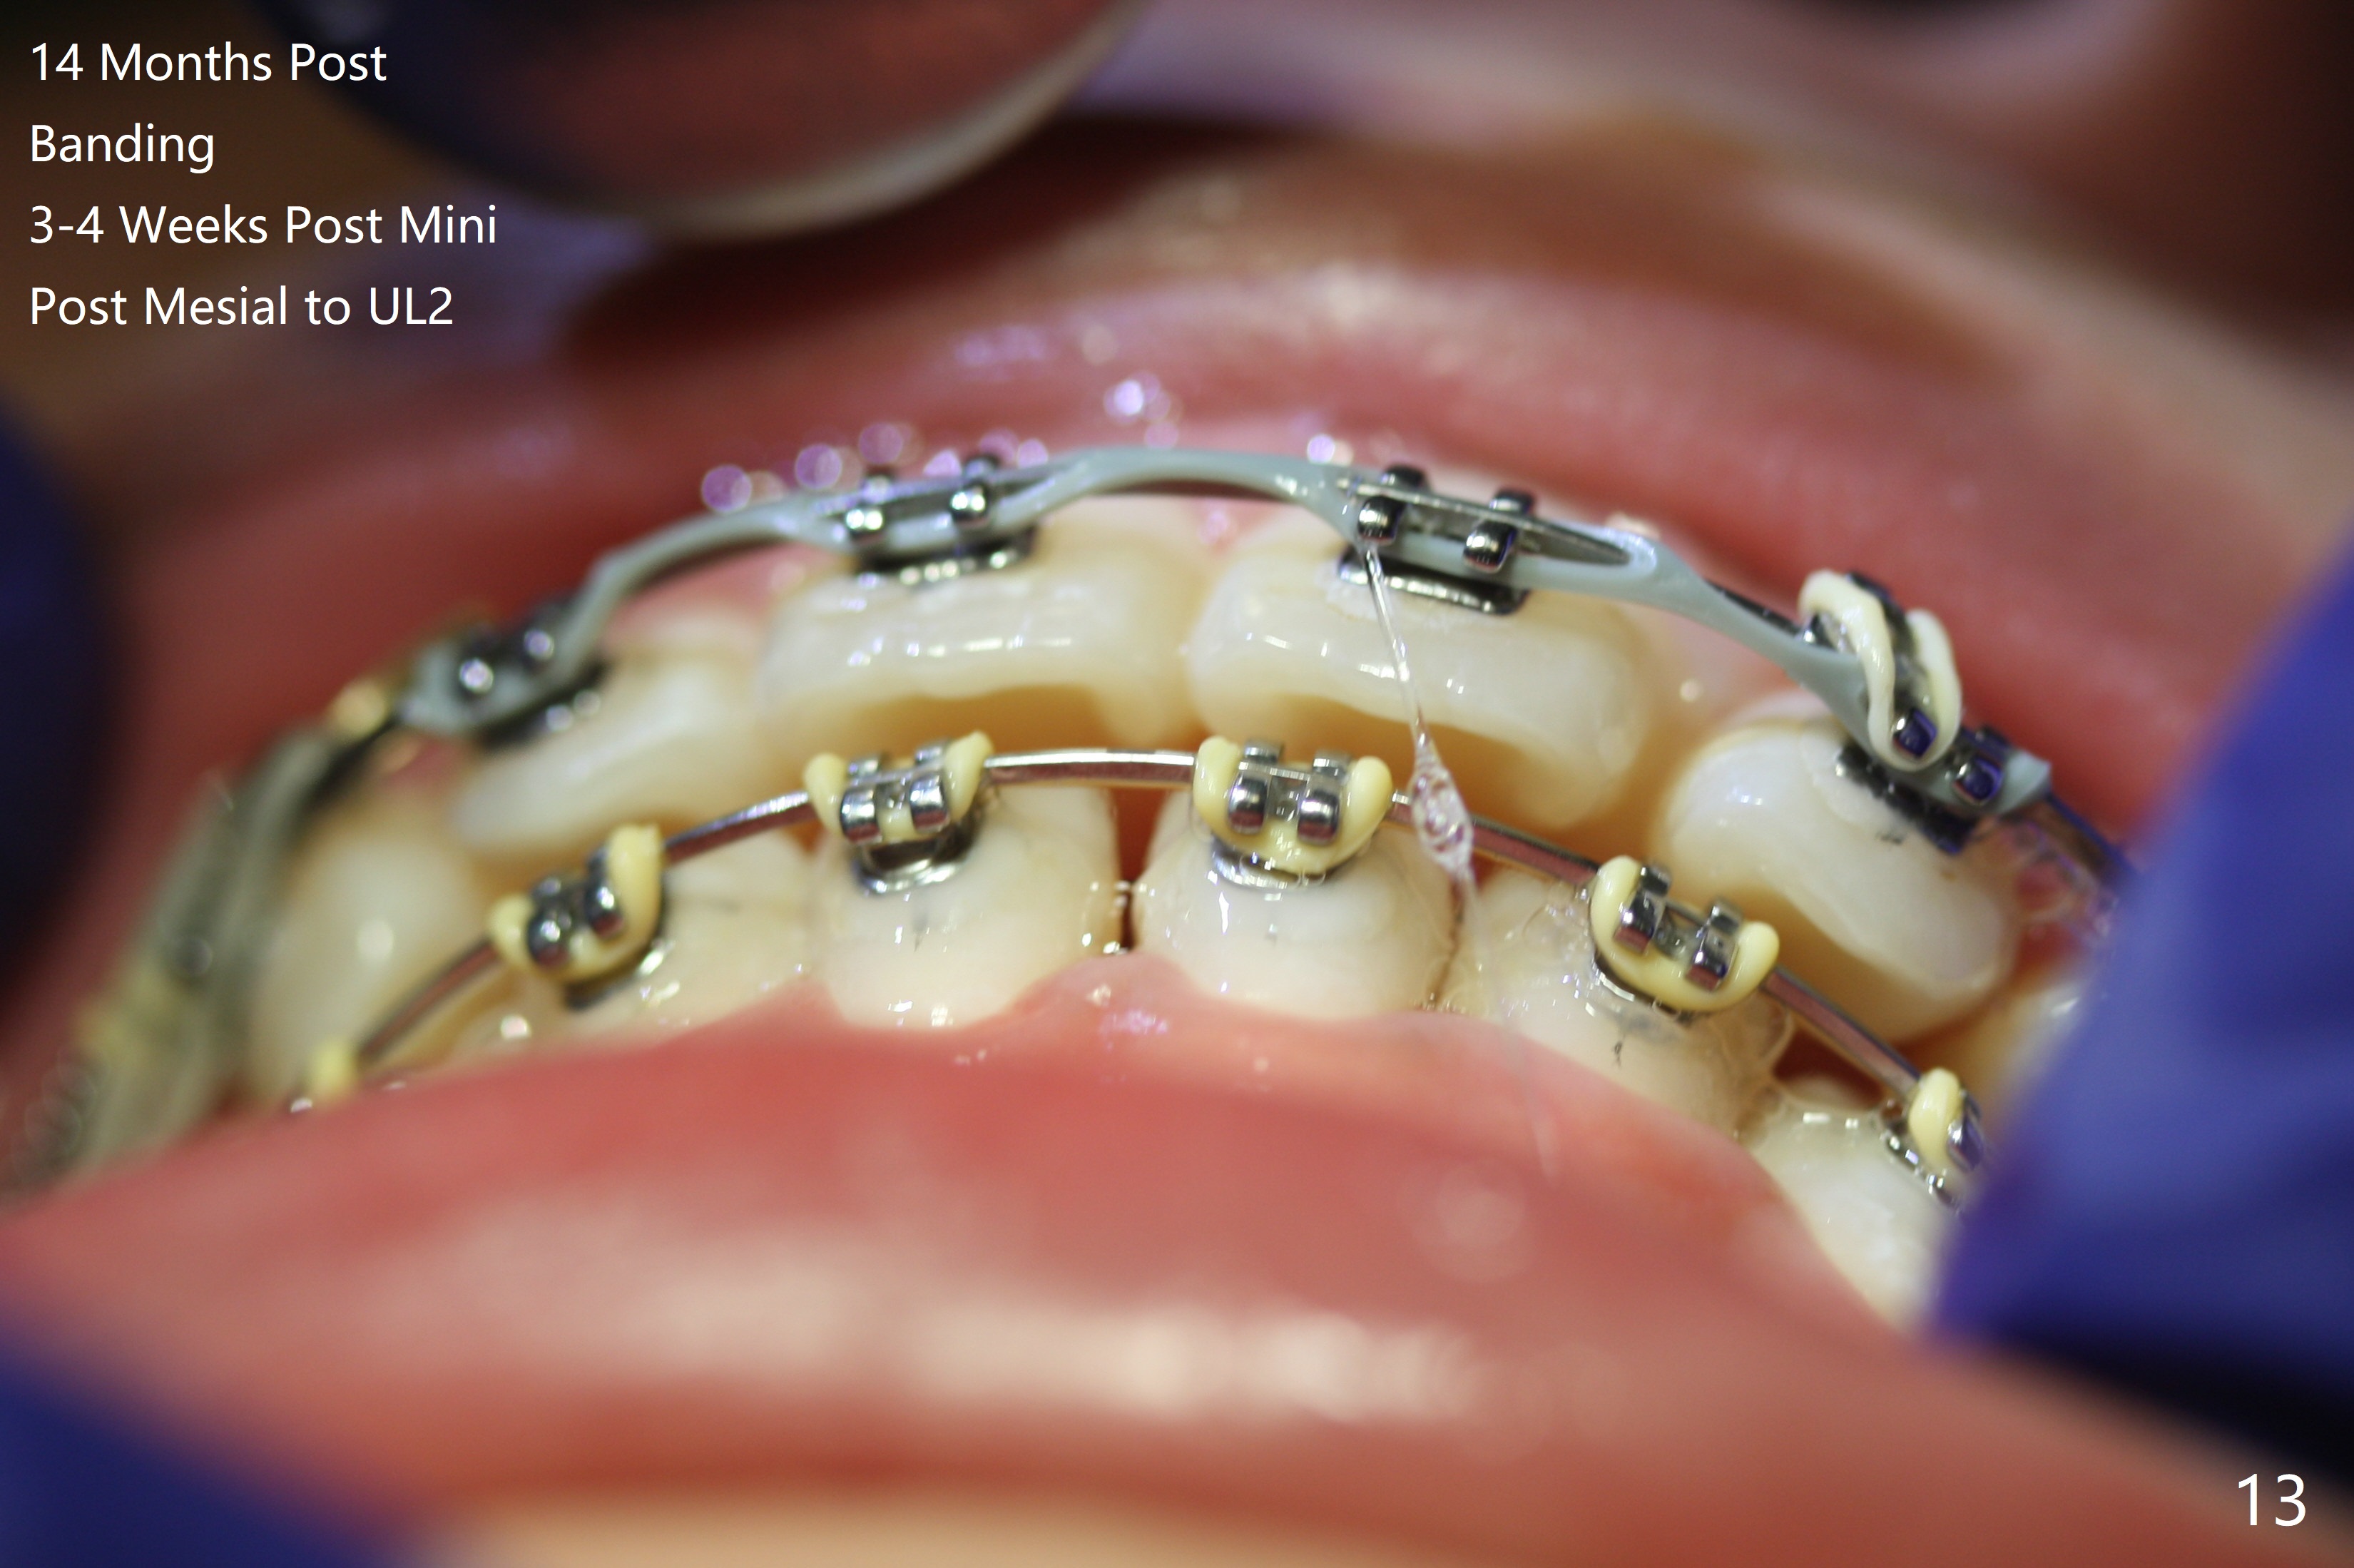

Thirteen months post banding, U dental midline apparently coincides with facial one, diastemata: UL2/3, UL6/7, L3-3, UL post detached, placed crimpable mini post mesial to UL2, closed spring UL2-7. Three-4 weeks later, diastema appears between UL1/2, while that of UL6/7 closes. Continue closed spring between UL2/7, while adding power chains U2-2 (Fig.12). To correct anterior overjet (Fig.13), Class II retraction is introduced bilaterally (Fig.14). After mesialization of LL3 (with Class I canine occlusion), L3-3 are being ligated as an anchor to mesialize LL5 (Fig.15). Occlusion appears to be Class II nearly 3 years post banding. Miniimplants are planned to distalize the upper dentition. Upper anterior PAs are taken to determine whether the roots of the upper anterior teeth have been resorbed. In fact, they are (Fig.16,17). Fortunately the anterior overjet does not look so severe. Orthodontic treatment should be terminated soon. Next case PAs should be taken prior to distalization.